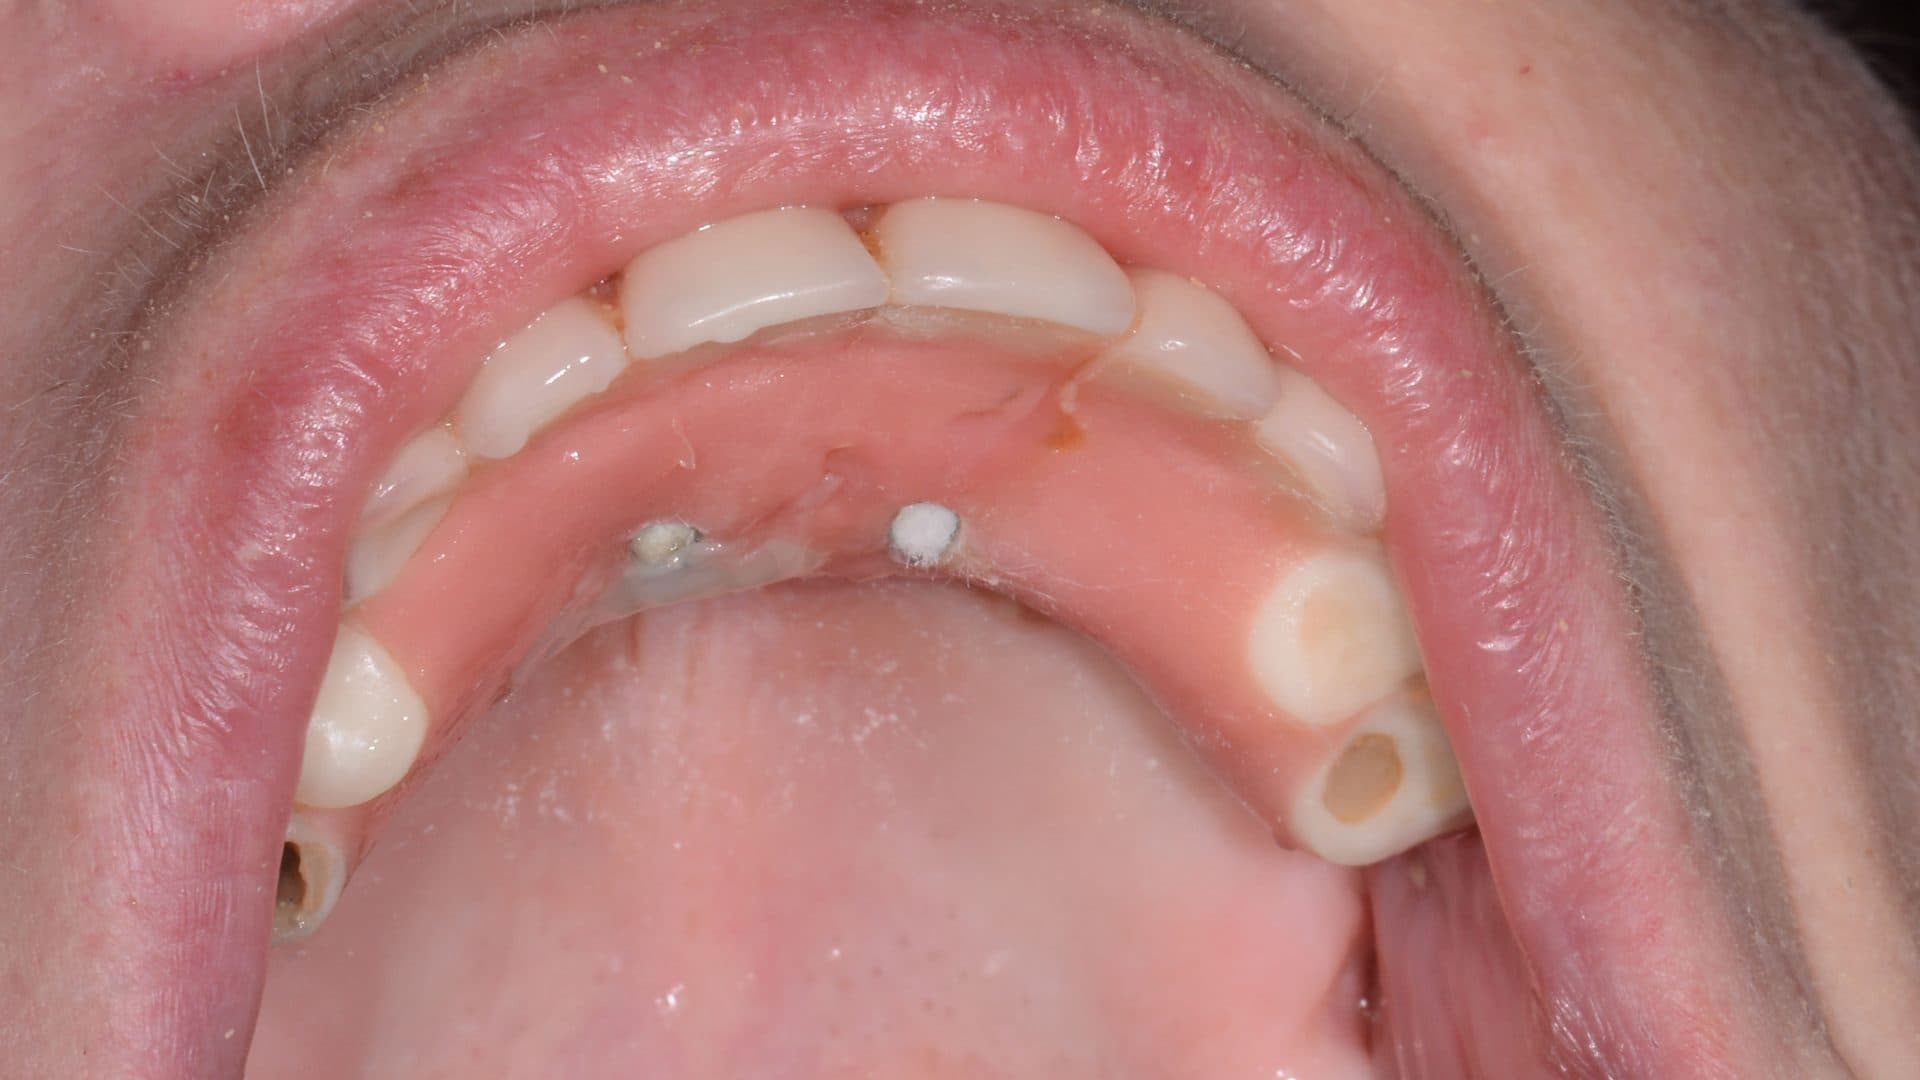

Here is a graphical overview of the ideal situation compared to poor standards with All-on-4 Plus® dental implants.

Ideal Situation

Poor Standards